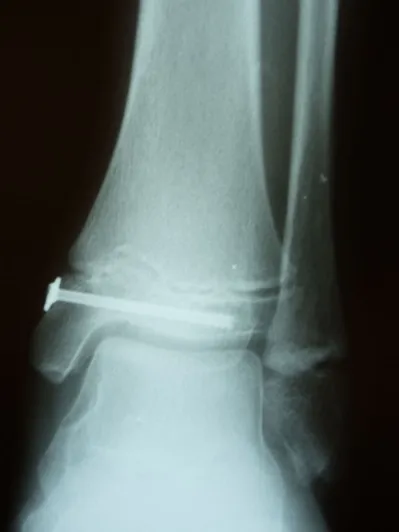

Post- surgical repair of the injury with screws traversing the injured area to allow good reduction and healing without affecting active growth plate areas.

These are post-operative x-rays after repair of the fracture using screws that remain permanently in most cases but does not cross the growth plate to allow healing of the fracture without affecting the growth of the leg bone. Bone healing typically takes 6-8 weeks.